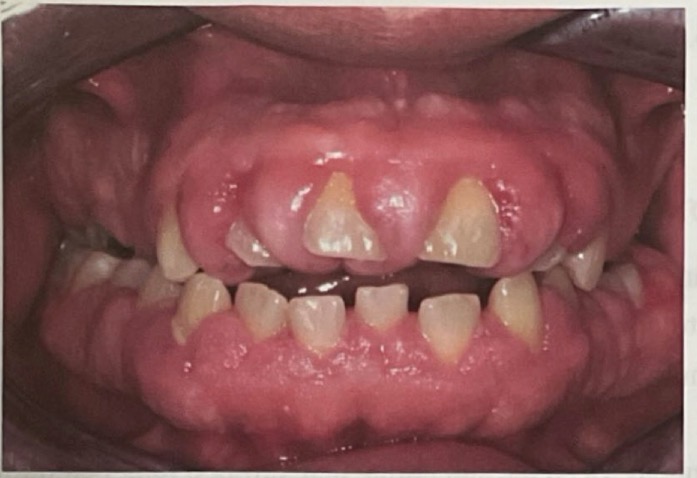

BN CÓ GAI NƯỚU TĂNG SINH, SƯNG TO, CẮNG BÓNG

SỜ DAI, KHÔNG ĐAU, KHÔNG CHẢY MÁU *

CHẨN ĐOÁN

TRIỂN DƯỠNG NƯỚU DO THUỐC PHENYTOIN

TRIỂN DƯỠNG NƯỚU DO DÙNG THUỐC PHENYTOIN

CHẨN ĐOÁN?